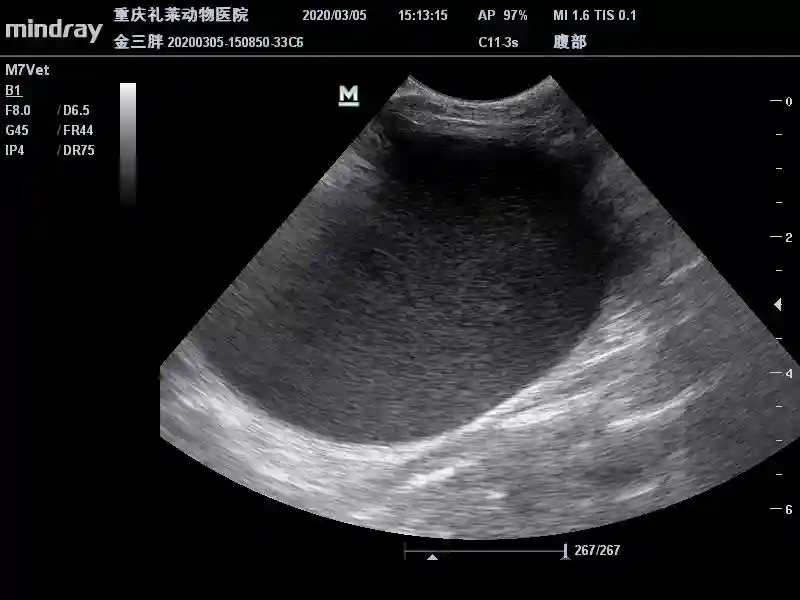

腹部彩超:

腹部彩超显示:膀胱内呈散在高回声声影,其他暂未见异常。

3月13日B超复查

膀胱内呈散在高回声声影。